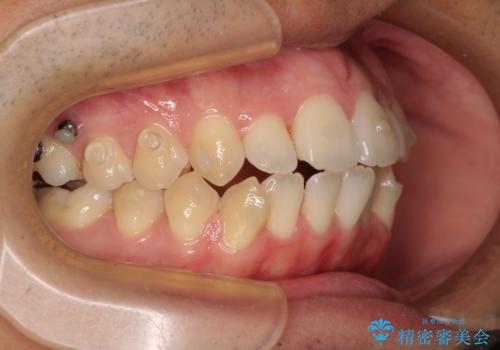

開咬とデコボコを整える インビザライン矯正治療

- 前歯の開咬と叢生を気にして来院された患者様です。

開咬の治療は、前歯を閉じるように動かすとともに、上下臼歯を圧下(骨内にめり込ませる)させることで進めて行きます。

インビザラインは臼歯の圧下を効果的に行えるため、インビザラインを用いて矯正治療を行うこととしました。また、アンカースクリューを用いて、口元の突出感の改善を図りました。